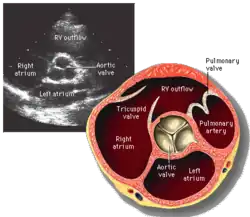

La valve aortique est l'une des quatre valves du cœur située à la jonction entre le ventricule gauche et l'aorte ascendante.

La valve aortique est située en bas du bulbe de l'aorte au-dessus de la chambre de chasse du ventricule gauche au niveau de l'orifice aortique.

Elle est constituée de trois valvules (ou cuspides) semi-lunaires formées par des replis de l'endocarde et attachées à l'anneau aortique :

- la valvule coronaire droite de la valve aortique (ou valvule semi-lunaire droite de la valve aortique),

- la valvule coronaire gauche de la valve aortique (ou valvule semi-lunaire gauche de la valve aortique),

- la valvule semi-lunaire postérieure de la valve aortique (ou valvule non coronaire de la valve aortique).

Elles sont séparées au niveau de leur attache par les commissures des valvules semi-lunaires de la valve aortique.

L'évaluation anatomique et fonctionnelle peut s e réaliser par échocardiographie , par scanner ou IRM cardiaque et par cathétérisme vasculaire.